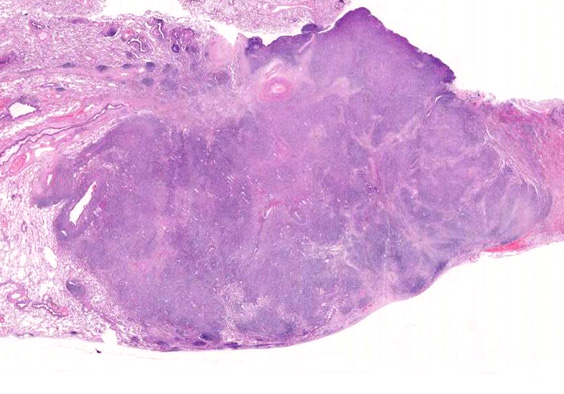

• 組織学的に,LyGは,様々な割合のリンパ球と大きなEBV+芽球からなる血管中心の浸潤を特徴としており,その中にはHRSに類似した特徴を示すものが出現する. 血管浸潤とそれに伴う多量の凝固壊死が典型的な所見である.

血管周囲性に大型類円形核や不整形核をもつ腫瘍細胞がシート状密に浸潤増殖している. Mitosisが多く認められる.細血管閉塞や破壊の所見がある.

間質にもシート状の腫瘍細胞浸潤がある. 大小 pleomorphicな傾向.(A, B). necrosisが認められる(C). 細気管支上皮直下まで密な浸潤あり, 小型リンパ球が混在している.(D)

血管中心性浸潤. 障害された血管内に血栓が形成されている.CD20陽性細胞がシート状密に浸潤, CD3陽性T細胞が多く混在している. EBER-ISH陽性 EBV感染細胞が多数認められ, >50 hpf, 定義より Grade3となる. 陽性細胞のサイズは大小さまざまであることに注意.

VATS採取標本肉眼腫瘤割面像腫瘤組織ルーペ像

病理組織所見